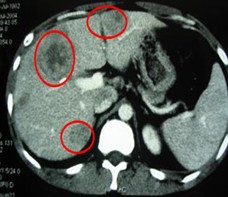

男,63岁,原发性肝癌晚期。AFP入院时为13000ng/L, 右肝区巨大肿瘤约为13×10=130 cm2。治疗方案:介入栓塞一个月后肝动脉插管皮下置泵灌注今又生和5-FU。治疗后:腹胀,腹痛消失,食欲增加,体重有所增加。AFP介入栓塞后为6000ng/L,灌注今又生和5-FU后为4ng/L,右肝肿瘤缩小至3×2cm。

治疗前

治疗后